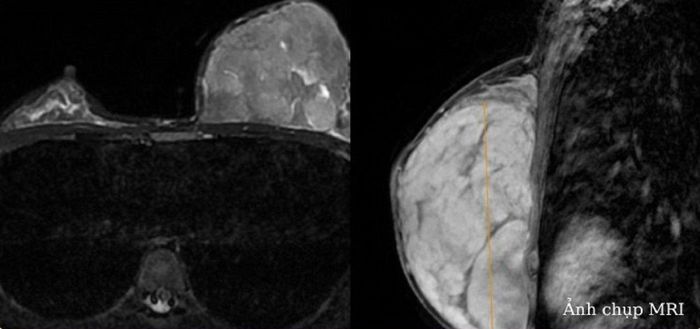

Một bên ngực to bất thường, cô gái 22 tuổi bất ngờ phát hiện khối u to gần 1 gang tay.

Quá trình siêu âm vú, bác sĩ nhận thấy hình ảnh tăng âm, tăng kích thước tuyến vú trái. Chụp MRI tuyến vú thấy khối u lớn nhu mô vú trái, không xân lấn thành ngực, kích thước 124x87x64 mm.